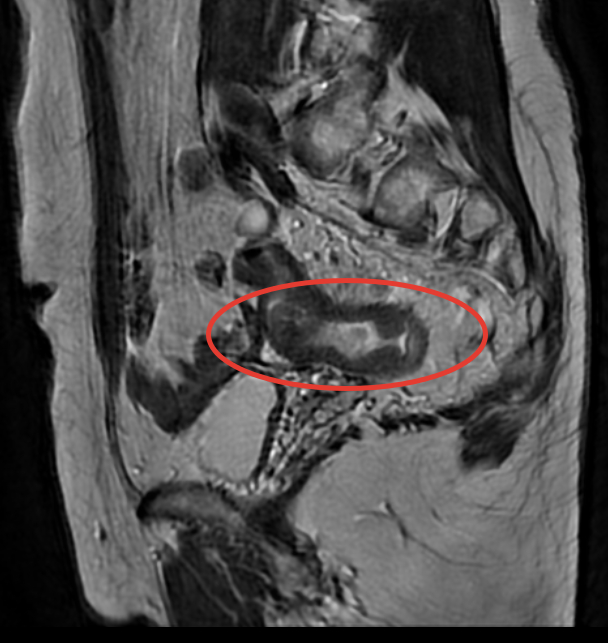

Год назад мне поставили страшный диагноз. Протоковый рак головки поджелудочной железы. Сама по себе болячка, ну, скажем, так себе…и осложнялось все тем, что были поражены прилегающие вены, артерии.

После прохождения 12 курсов химии эта гадость не уменьшилась, более того, мигрировала еще больше на артерии…Блохина и другие московские клиники, клиники Южной Кореи, Израиля, куда я отправляла свои СКТ и МРТ, признали опухоль неоперабельной - все отказывали в операции. Пипец был полный…